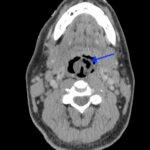

Epiglottitis is historically known to be a disease of childhood. However, since the implementation of the Haemophilus influenzae type B vaccination, there has been an increasing incidence within the adult population. This is a case report of a 36-year-old male who presented to the emergency department (ED) in severe respiratory distress with complaints of a sore throat, shortness of breath, odynophagia, dysphagia, and hoarseness. Physical exam revealed biphasic stridor, tachycardia, tachypnea, and an erythematous uvula. Imaging of his neck revealed findings consistent with epiglottitis containing nonspecific air. The patient was rapidly intubated, started on broad spectrum antibiotics and dexamethasone. He was admitted for intensive medical management with Otolaryngology consultation. This case report highlights the importance of rapid recognition and diagnosis of epiglottitis in an adult population to prevent morbidity and mortality.